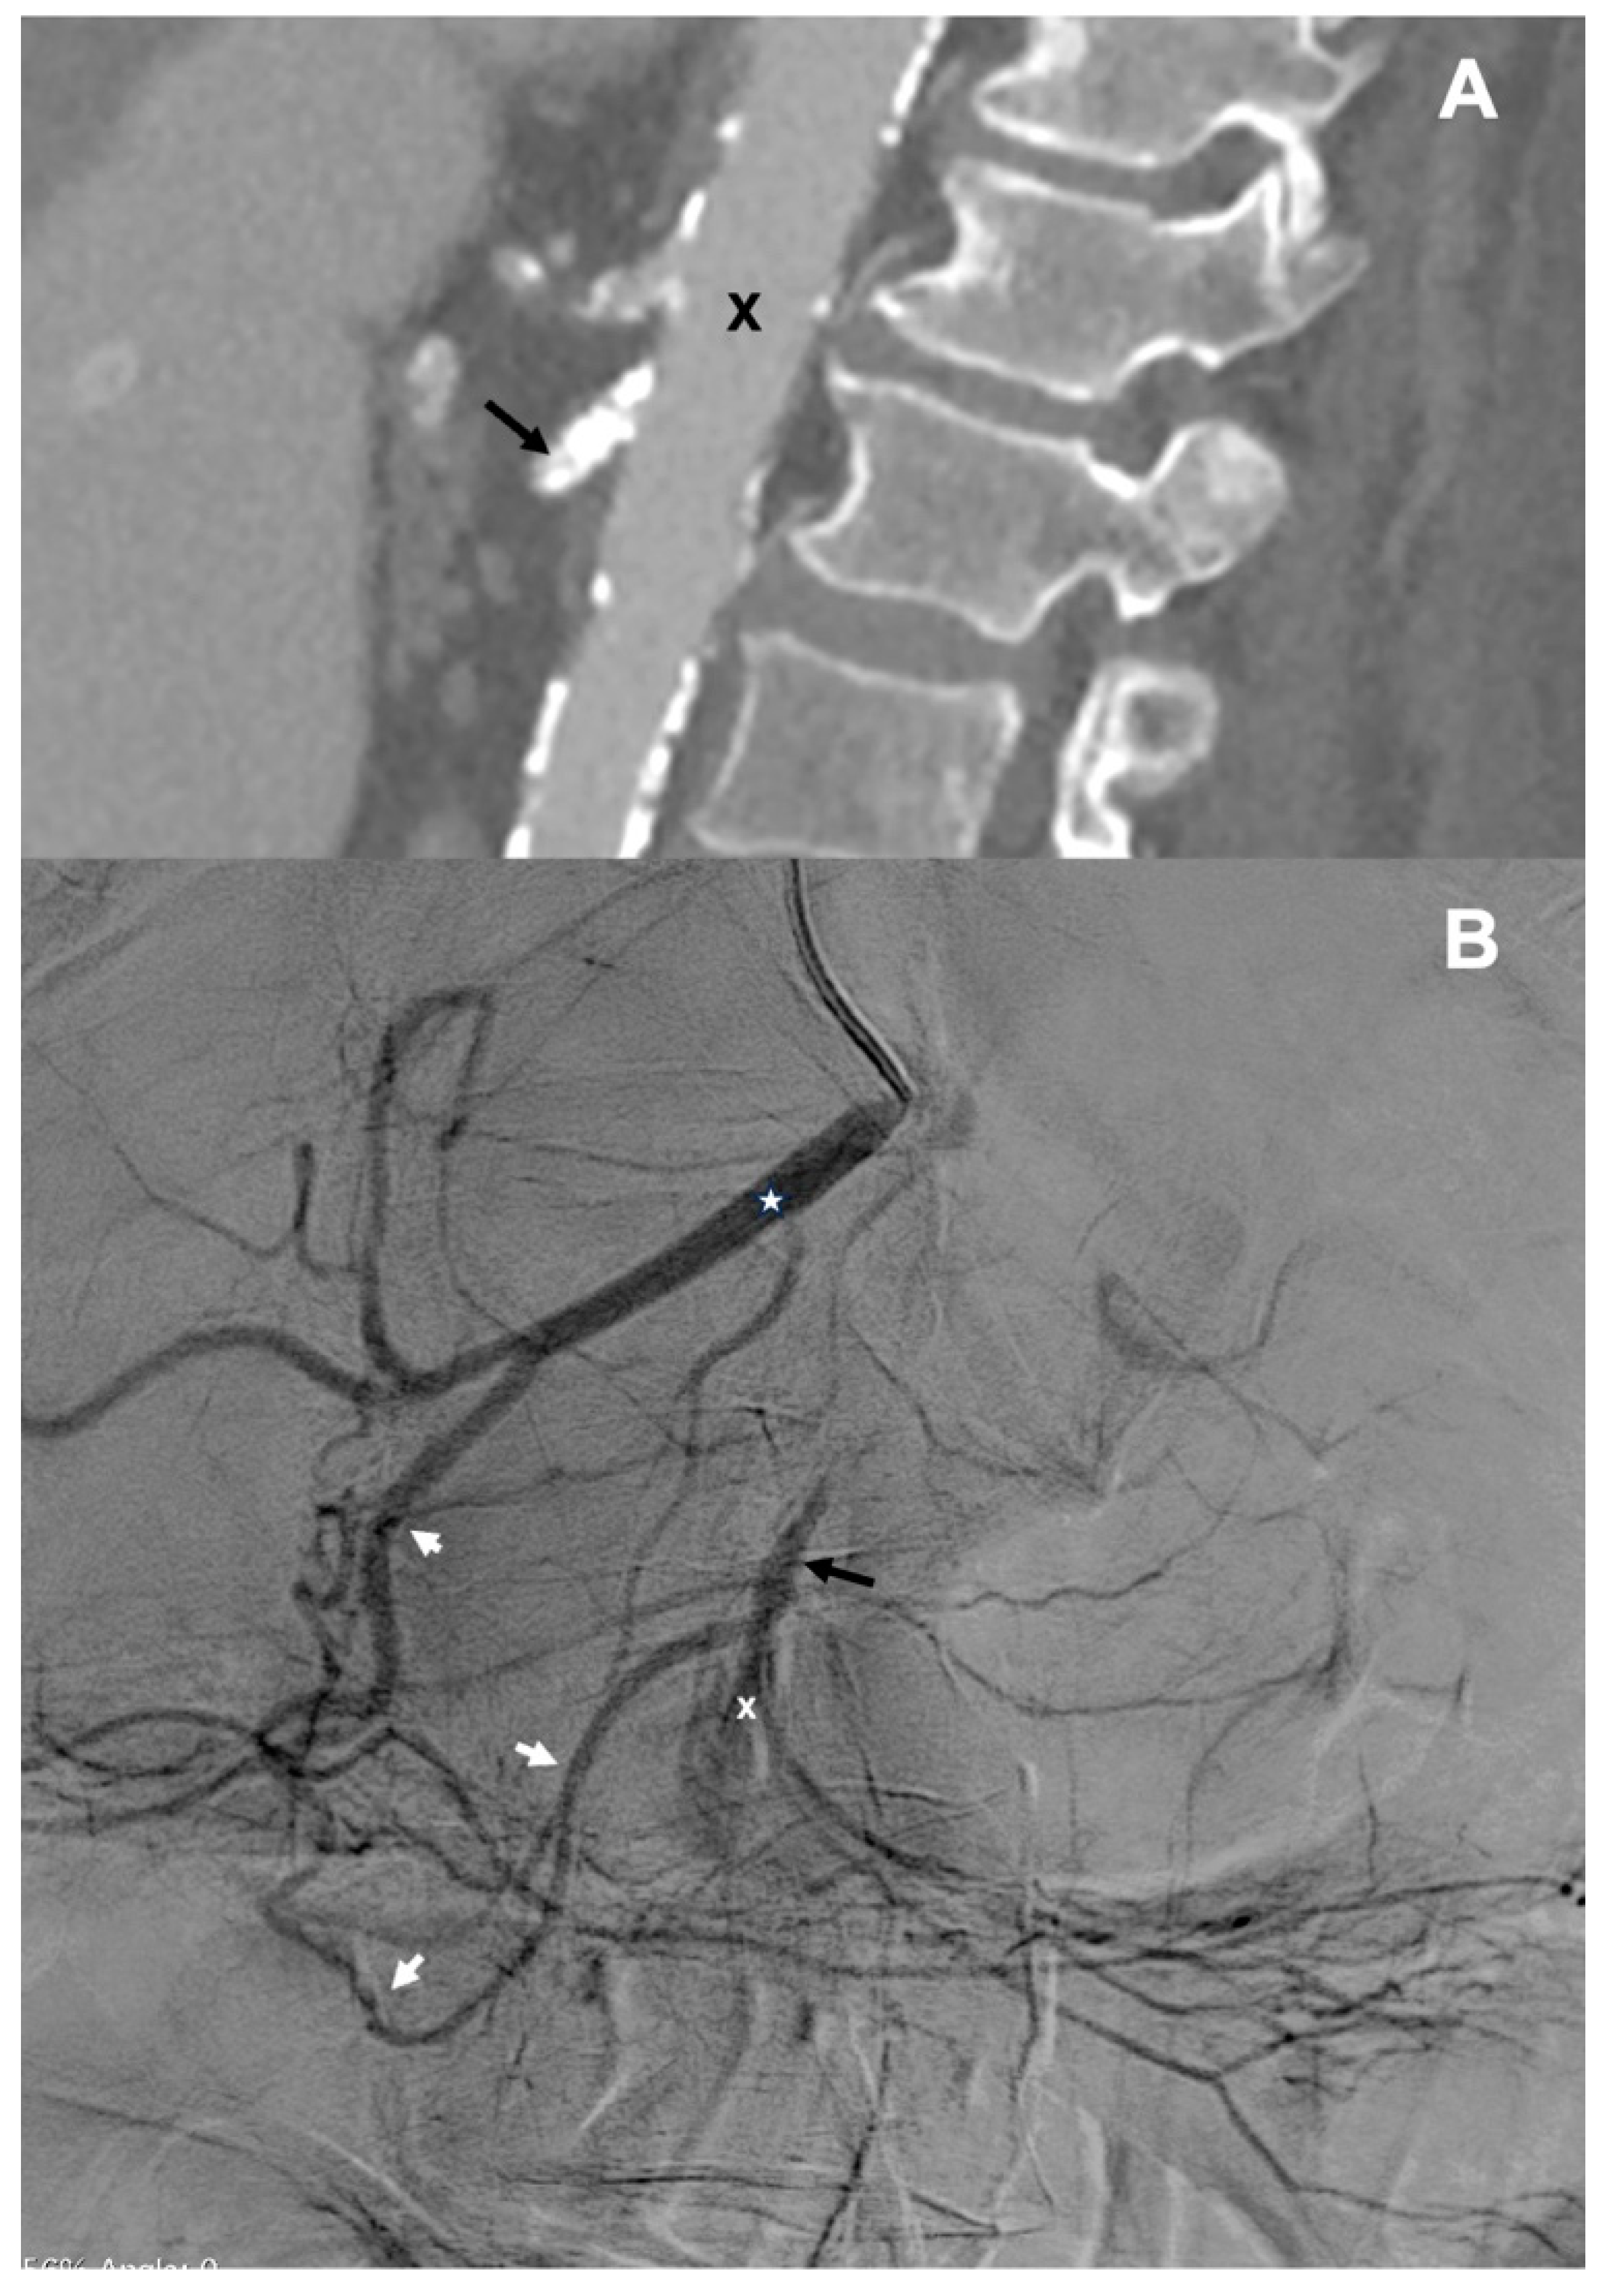

Here, we present the case of percutaneous retrograde recanalization of an occluded SMA in the patient presenting with ABI. An 82-year-old female patient developed progressing abdominal symptoms during hospital stay after thrombarterectomy of the femoral artery, which was performed for the treatment of critical lower limb ischemia. CT angiography revealed calcified plaques in the SMA, located 3 mm distally from the aorta (Figure 1A). This lesion completely occluded proximal part the SMA. This examination also demonstrated patent celiac trunk, wide common hepatic artery (CHA), and patent, although narrow, gastroduodenal artery (GDA). Distal branches of the SMA were not visible. The overall clinical picture suggested thrombosis of the SMA resulting in bowel ischemia.

Figure 1. A – CT angiography of the aorta (X) and visceral arteries (sagittal projection): a highly calcified plaque 3 mm from the aorta, occluding proximal segment of the superior mesenteric artery (black arrow); B – Catheter angiography of the celiac trunk – common hepatic artery (asterisk) and gastroduodenal artery (white arrows) and retrograde inflow to the proximally occluded superior mesenteric artery (black arrow) and no inflow to the distal part of superior mesenteric artery (X).